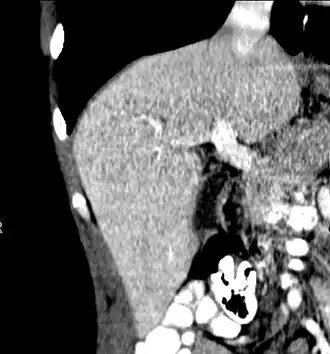

The diagnosis of liver disease is made by liver function tests, groups of blood tests, that can readily show the extent of liver damage. If infection is suspected, then other serological tests will be carried out. A physical examination of the liver can only reveal its size and any tenderness, and some form of imaging such as an ultrasound or CT scan may also be needed.

-

Axial CT image showing anomalous hepatic veins coursing on the liver's subcapsular anterior surface[74] -

Maximum intensity projection (MIP) CT image as viewed anteriorly showing the anomalous hepatic veins coursing on the anterior surface of the liver -

Lateral MIP view in the same patient as previous image -

A CT scan in which the liver and portal vein are shown